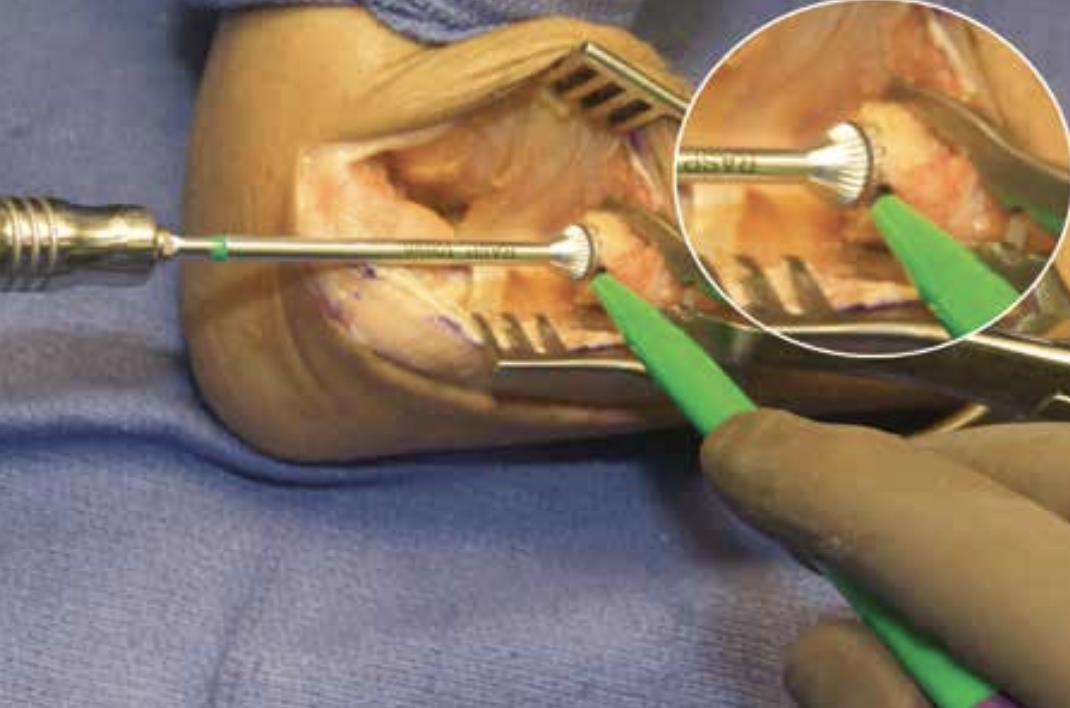

• Neck planing

• prepare the respected end of the radius using the planer